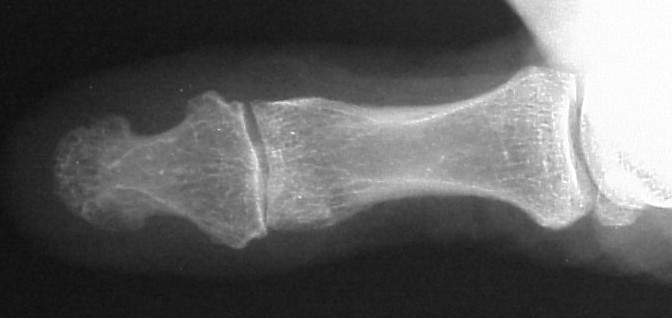

Plain films showed resorption of the distal two thirds of the distal phalanx:

Click for larger image